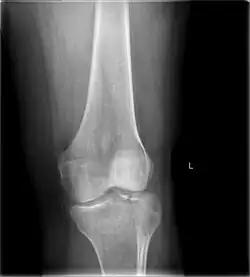

Tibial plateau fracture

![]() | |

| A severe tibial plateau fracture with an associated fibular head fracture | |